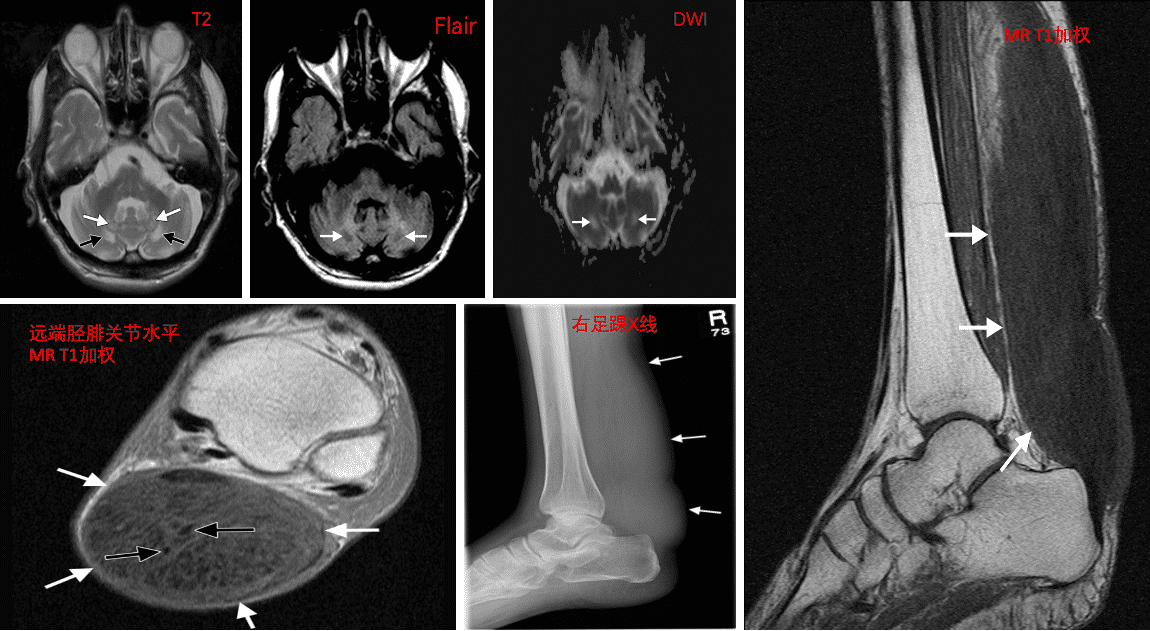

一、病例特点患者祁x,男性,慢性进展性病程;临床表现为缓慢进展性行走困难,伴躯体平衡障碍;查体:神清,轻度认知和语言障碍,肌张力增高,双侧深部腱反射活跃,巴宾斯基反射和踝关节阵挛阳性。双侧跟腱卵形大小、坚硬、光滑且无痛的肿块。既往史:2年前突发下肢无力和右踝关节后部疼痛肿胀而被误诊为“右下肢丹毒”,治疗后症状有所改善。个人史及家族史:他发育正常,无新生儿黄疸、白内障或婴儿腹泻病史。他读完了小学、初中。他的父母是非血缘关系,没有明显的家族史。实验室检查显示没有异常,包括肝肾功能、血清电解质、甘油三酯和胆固醇水平。脑电图检查显示由 θ 波和 δ 波组成的缓慢背景活动,偶尔伴有高压活动。基因检测分析提示: CYP27A1 突变!二、神经影像右踝侧X光显示,远端胫骨和跟腱区域的跟骨处有一个明显的延长软组织肿块(箭头)矢状T1加权(重复时间毫秒/回声时间毫秒,805/11)中线MRI影像显示跟腱的梭状增大,该腱前缘凸出(箭头),与肌肉等强度。远端胫腓关节水平的轴向中等加权(1800/15)共振图像显示跟腱(白色箭头)弥漫性肿大,肌腱与肌肉等强度,内夹有低信号强度肌腱束(黑色箭头)。桥脑水平的轴向T2加权(3000/86)磁共振图像显示,齿状核(白色箭头)和周围深小脑白质(黑色箭头)均有斑驳的高强度。小脑萎缩也可见。小脑水平的轴向T2加权FLAIR(8400/114)磁共振图像显示深部小脑白质的低强度(箭头)。轴向扩散加权(8400/114,b = 1000秒/毫米) 2)共振成像和(b)通过小脑水平获得的对应表观扩散系数图显示,深部小脑白质的扩散率增加(箭头)。三、临床印象脑腱黄瘤病四、干预及转归患者接受鹅去氧胆酸治疗,250mg,每天3次。迄今为止,患者的跟腱双侧黄瘤已开始减轻,他的神经功能障碍没有进一步恶化,但尚未改善。Tips 心情驿站